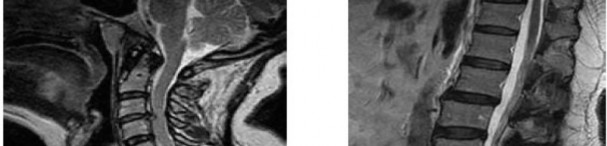

Question 7:

A 65-year-old man presents with progressive clumsiness in his hands, difficulty buttoning his shirt, and a broad-based gait. A T2-weighted MRI shows spinal cord compression with intrinsic cord signal change at C4-C5. Which of the following MRI findings is associated with the poorest prognosis for neurological recovery after surgical decompression in cervical spondylotic myelopathy?

Correct Answer: T1 hypointensity corresponding to the T2 hyperintensity

Explanation:

In cervical spondylotic myelopathy, the presence of T1 hypointensity corresponding to a T2 hyperintense lesion indicates myelomalacia or cystic necrosis of the spinal cord. This finding is a strong predictor of poor functional recovery following surgical decompression.